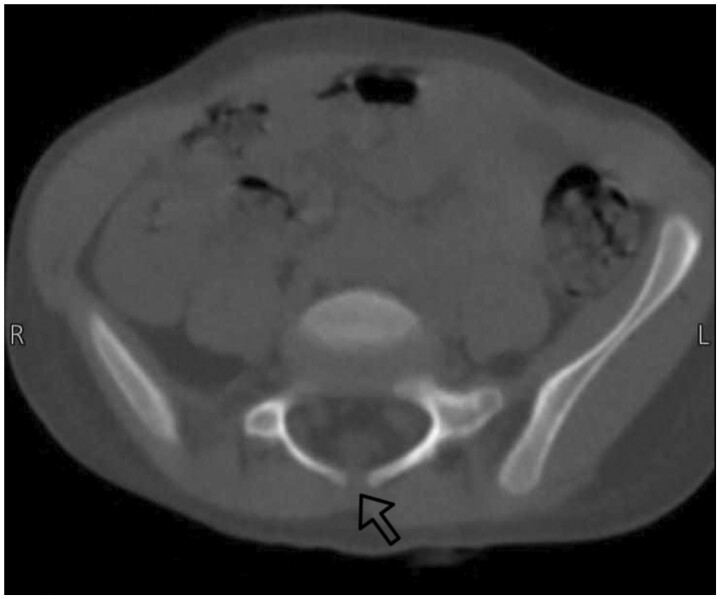

Fibular hemimelia (FH) is a rare congenital abnormality where the fibula is either totally or partially absent. It can occur alone or alongside other skeletal malformations, and in very few cases, it may occur along with non-skeletal anomalies. A 4-year-old female was diagnosed with unilateral right-sided FH, accompanied by limb shortening, a right-side ankle deformity, valgus foot, and 3 lateral rays that had been totally absent since the first week of birth. And she was incidentally diagnosed with spina bifida occulta at a 3-year-old age. FH is most commonly unilateral and mostly affects the right side, leads to a limb-length discrepancy, and maybe comes as a symptom of a syndrome such as Foetus-Fibula-Ulna syndrome and so on. Risk factors include prenatal history, drugs, and no supplementation intake. Together, these elements could be a contributing factor to our condition. The congenital limb abnormalities may be discovered during pregnancy by sonography. If present, other investigations need to be done to differentiate the diagnosis. Treatment according to degree: mild, moderate, and severe cases. In our case, the type 2 FH characteristic was shown by sonography, accompanied by limb shortening, lateral rays absent, and a non-skeletal anomaly (spina bifida). These anomalies very rarely come with each other at the same time. To the best of our knowledge, this case is exceptional in that FH is present at birth alongside spina bifida.